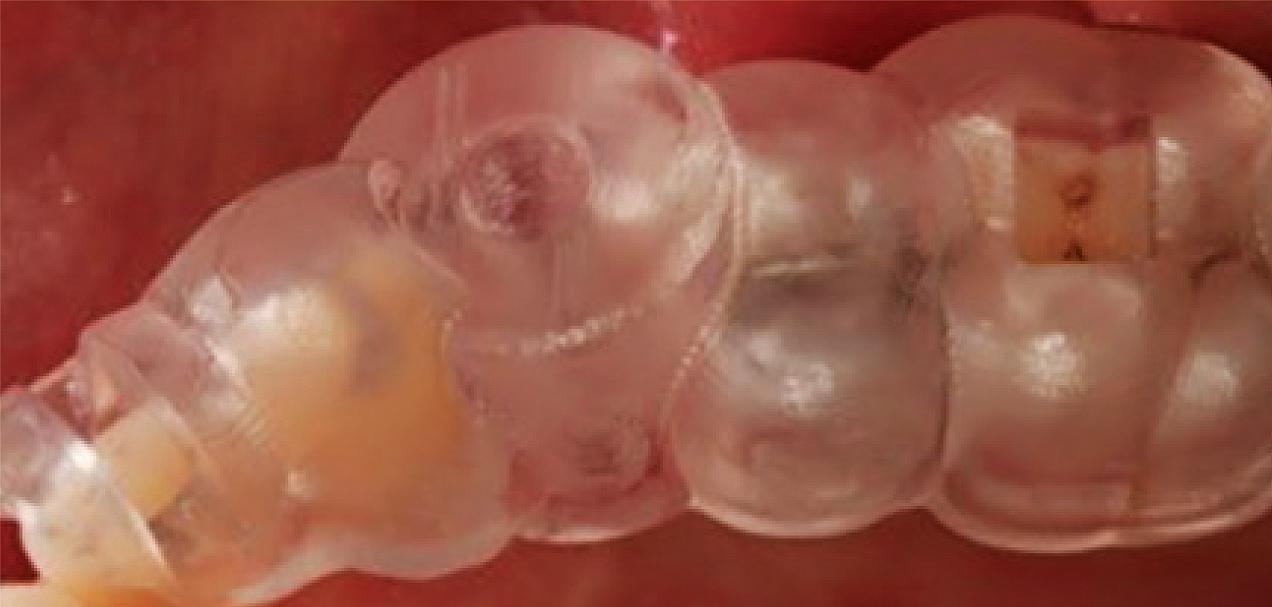

Figure 1: Radiographic Image of implants do not demonstrate bone loss due to the bisecting angle of the radiograph taken.

Figure 2: Radiographic image in a paralleling technique of implants dem onstrate moderate peri-implantitis with bone loss that will necessitate treatment.